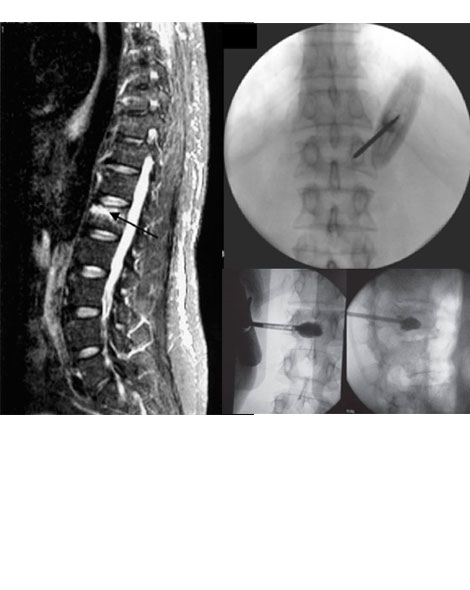

Resonancia Magnetica Nuclear (RMN).- Ayuda a identificar y diferenciar las fracturas agudas (con edema) de las fracturas crónicas.

Procedimiento se realiza en Sala de Operaciones y es necesario el uso de un equipo de rayos X portátil llamado (Arco en C y/o Tomógrafo).

...VERTEBROPLASTIA: